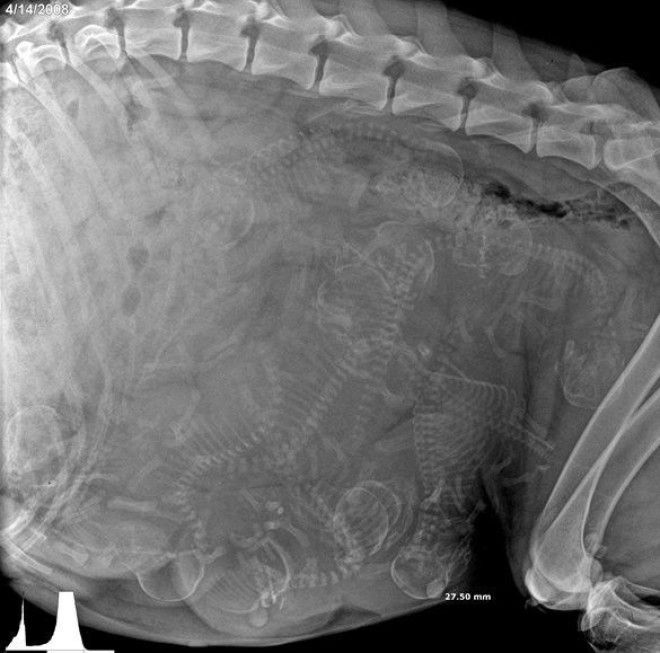

4. Еще одна кошка